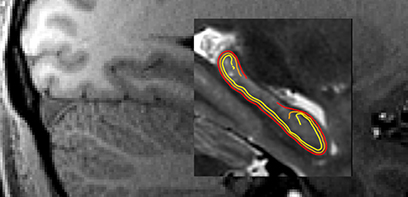

Study explores why South Asians have higher rates of heart disease

February 14, 2024

Research data provides a previously unrecognized link to explain why South Asians develop early and aggressive heart disease.